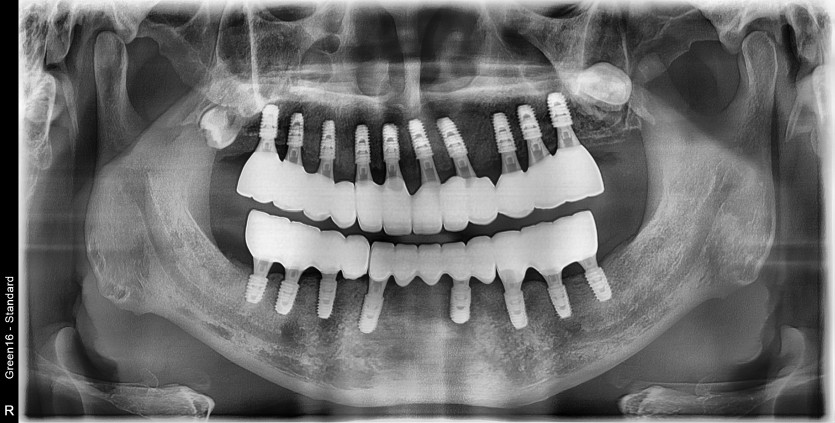

만 53세 전체 임플란트

전체 임플란트 증례입니다.

18개의 임플란트로 완성하였습니다.